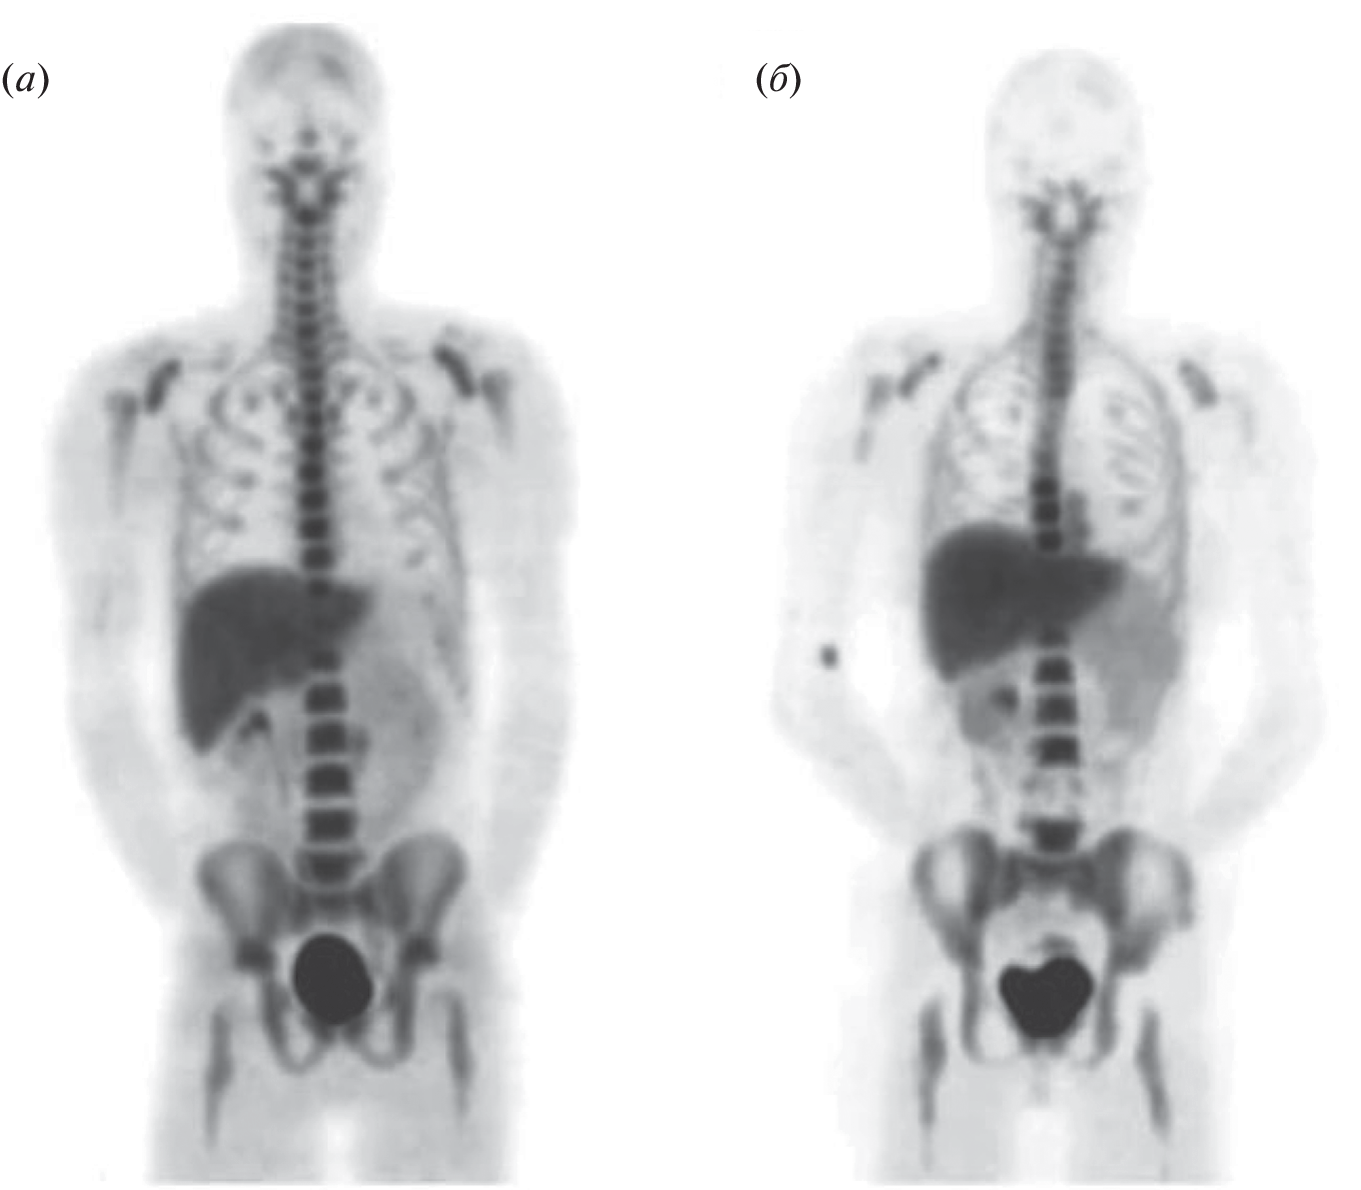

To date, the most common drug for the diagnosis of cancer tumors is [18F]-fluorodeoxyglucose, an radiopharmaceuticals for positron emission tomography diagnostics using the fact of increased glucose metabolism by cancer cells. At the same time, there are a number of cases where an approach based on glucose derivatives is not applicable. In many cases, inflammation or other benign processes are indistinguishable from tumor formations. For such cases of non-specificity of oncologies to glucose (not only tumor cells, but also healthy cells actively consume [18F]-fluorodeoxyglucose), the use of other metabolic pathways is required, which, in the case of a specific tumor in this organ, will be specific to the radiopharmaceuticals used.